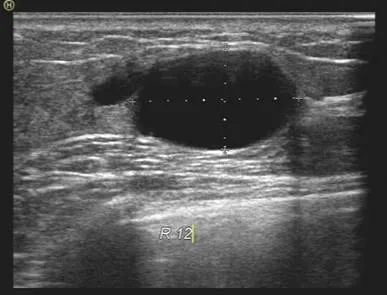

女性,32岁,来院行乳腺超声检查,超声所见如图

解读:该女性左乳下方(6点)可见一约0.6cm大小的低回声结节,界清,形态规则,未见明显血流信号。根据超声所见良性结节考虑,定期随访即可。